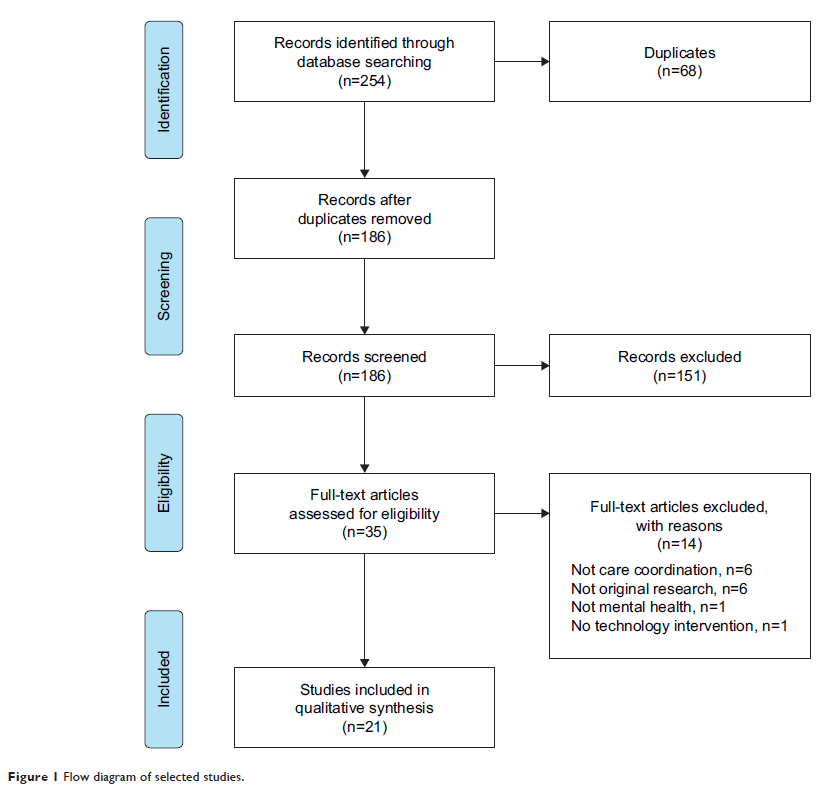

Review 简明总结

Use of technology for care coordination initiatives for patients with mental health issues: a systematic literature review

- 作者:Erin Falconer, David Kho, John P Docherty

- 期刊:Neuropsychiatric Disease and Treatment